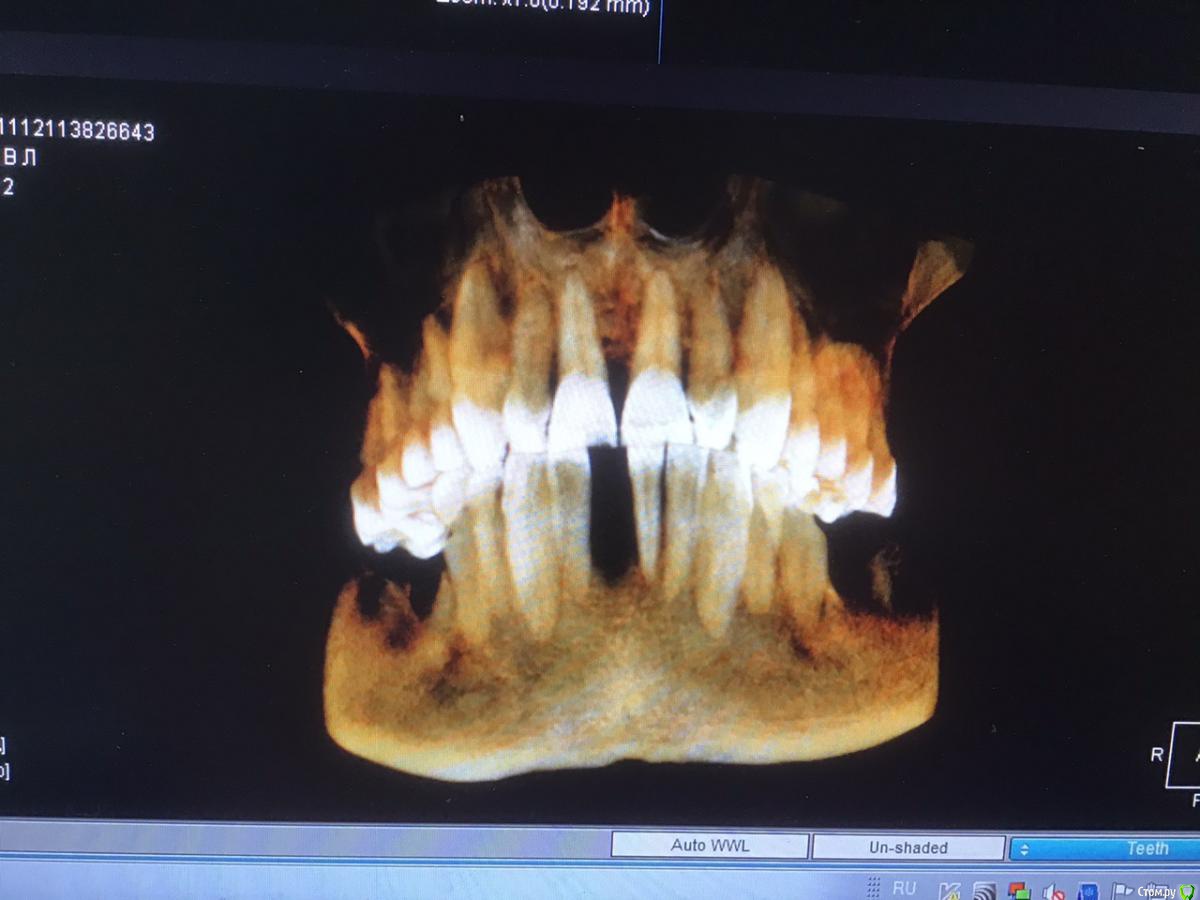

4lev Опубликовано 20 ноября, 2019 Поделиться Опубликовано 20 ноября, 2019 Здравствуйте! Хотелось бы получить совет. Были в 5 клиниках и все планы лечения разные. Нижняя челюсть. Справа все единодушны, а вот слева и во фронтальной зоне разногласия, боимся ошибиться. Пациент мужчина, 67 лет. Сделано КТ в одной из клиник, другие говорят, что плохое качество. Можно ли по этому исследованию принять решение? Заранее спасибо. Владимир.Ссылка для скачивания файлов: https://cloud.mail.ru/stock/iNXKZVqLzRqyfXzwbHJzDMVi . Ссылка на комментарий

4lev Опубликовано 20 ноября, 2019 Автор Поделиться Опубликовано 20 ноября, 2019 Справа внизу все единодушно предлагают 2 импланта.Слева варианты: 1.поставить 2 импланта с костной пластикой (стружка) у 7 зуба во время операции. 2. поставить только один имплант(6), так как для 7 недостаточно костной ткани и он не особо нужен. 3. поставить два импланта потом, когда восстановится кость после удаления зуба( а это было летом), а пока принимать кальций. Теперь впереди: 1. поставить один имплант. 2. удалить один зуб и поставить два импланта. 3. удалить три зуба и сделать мост на двух имплантах. В общем, предлагают эти варианты в разных комбинациях, голова кругом и не знаем какой вариант оптимальный. Еще в одном варианте предложено подпилить 2 верхних зуба, которые опустились и поставить на них циркониевые коронки, по 2 слева и справа. Буду благодарен за советы. Ссылка на комментарий

4lev Опубликовано 20 ноября, 2019 Автор Поделиться Опубликовано 20 ноября, 2019 Получилось только так, к сожалению Ссылка на комментарий